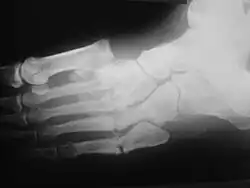

Oblique view X-ray in a 45-year-old male diabetic revealed a divergent, Lisfranc dislocation of the first metatarsal with associated lesser metatarsal fractures.

The same 45-year-old man with diabetes mellitus presented with a diffusely swollen, warm and non-tender left foot due to Charcot arthropathy. There are no changes to the skin itself.